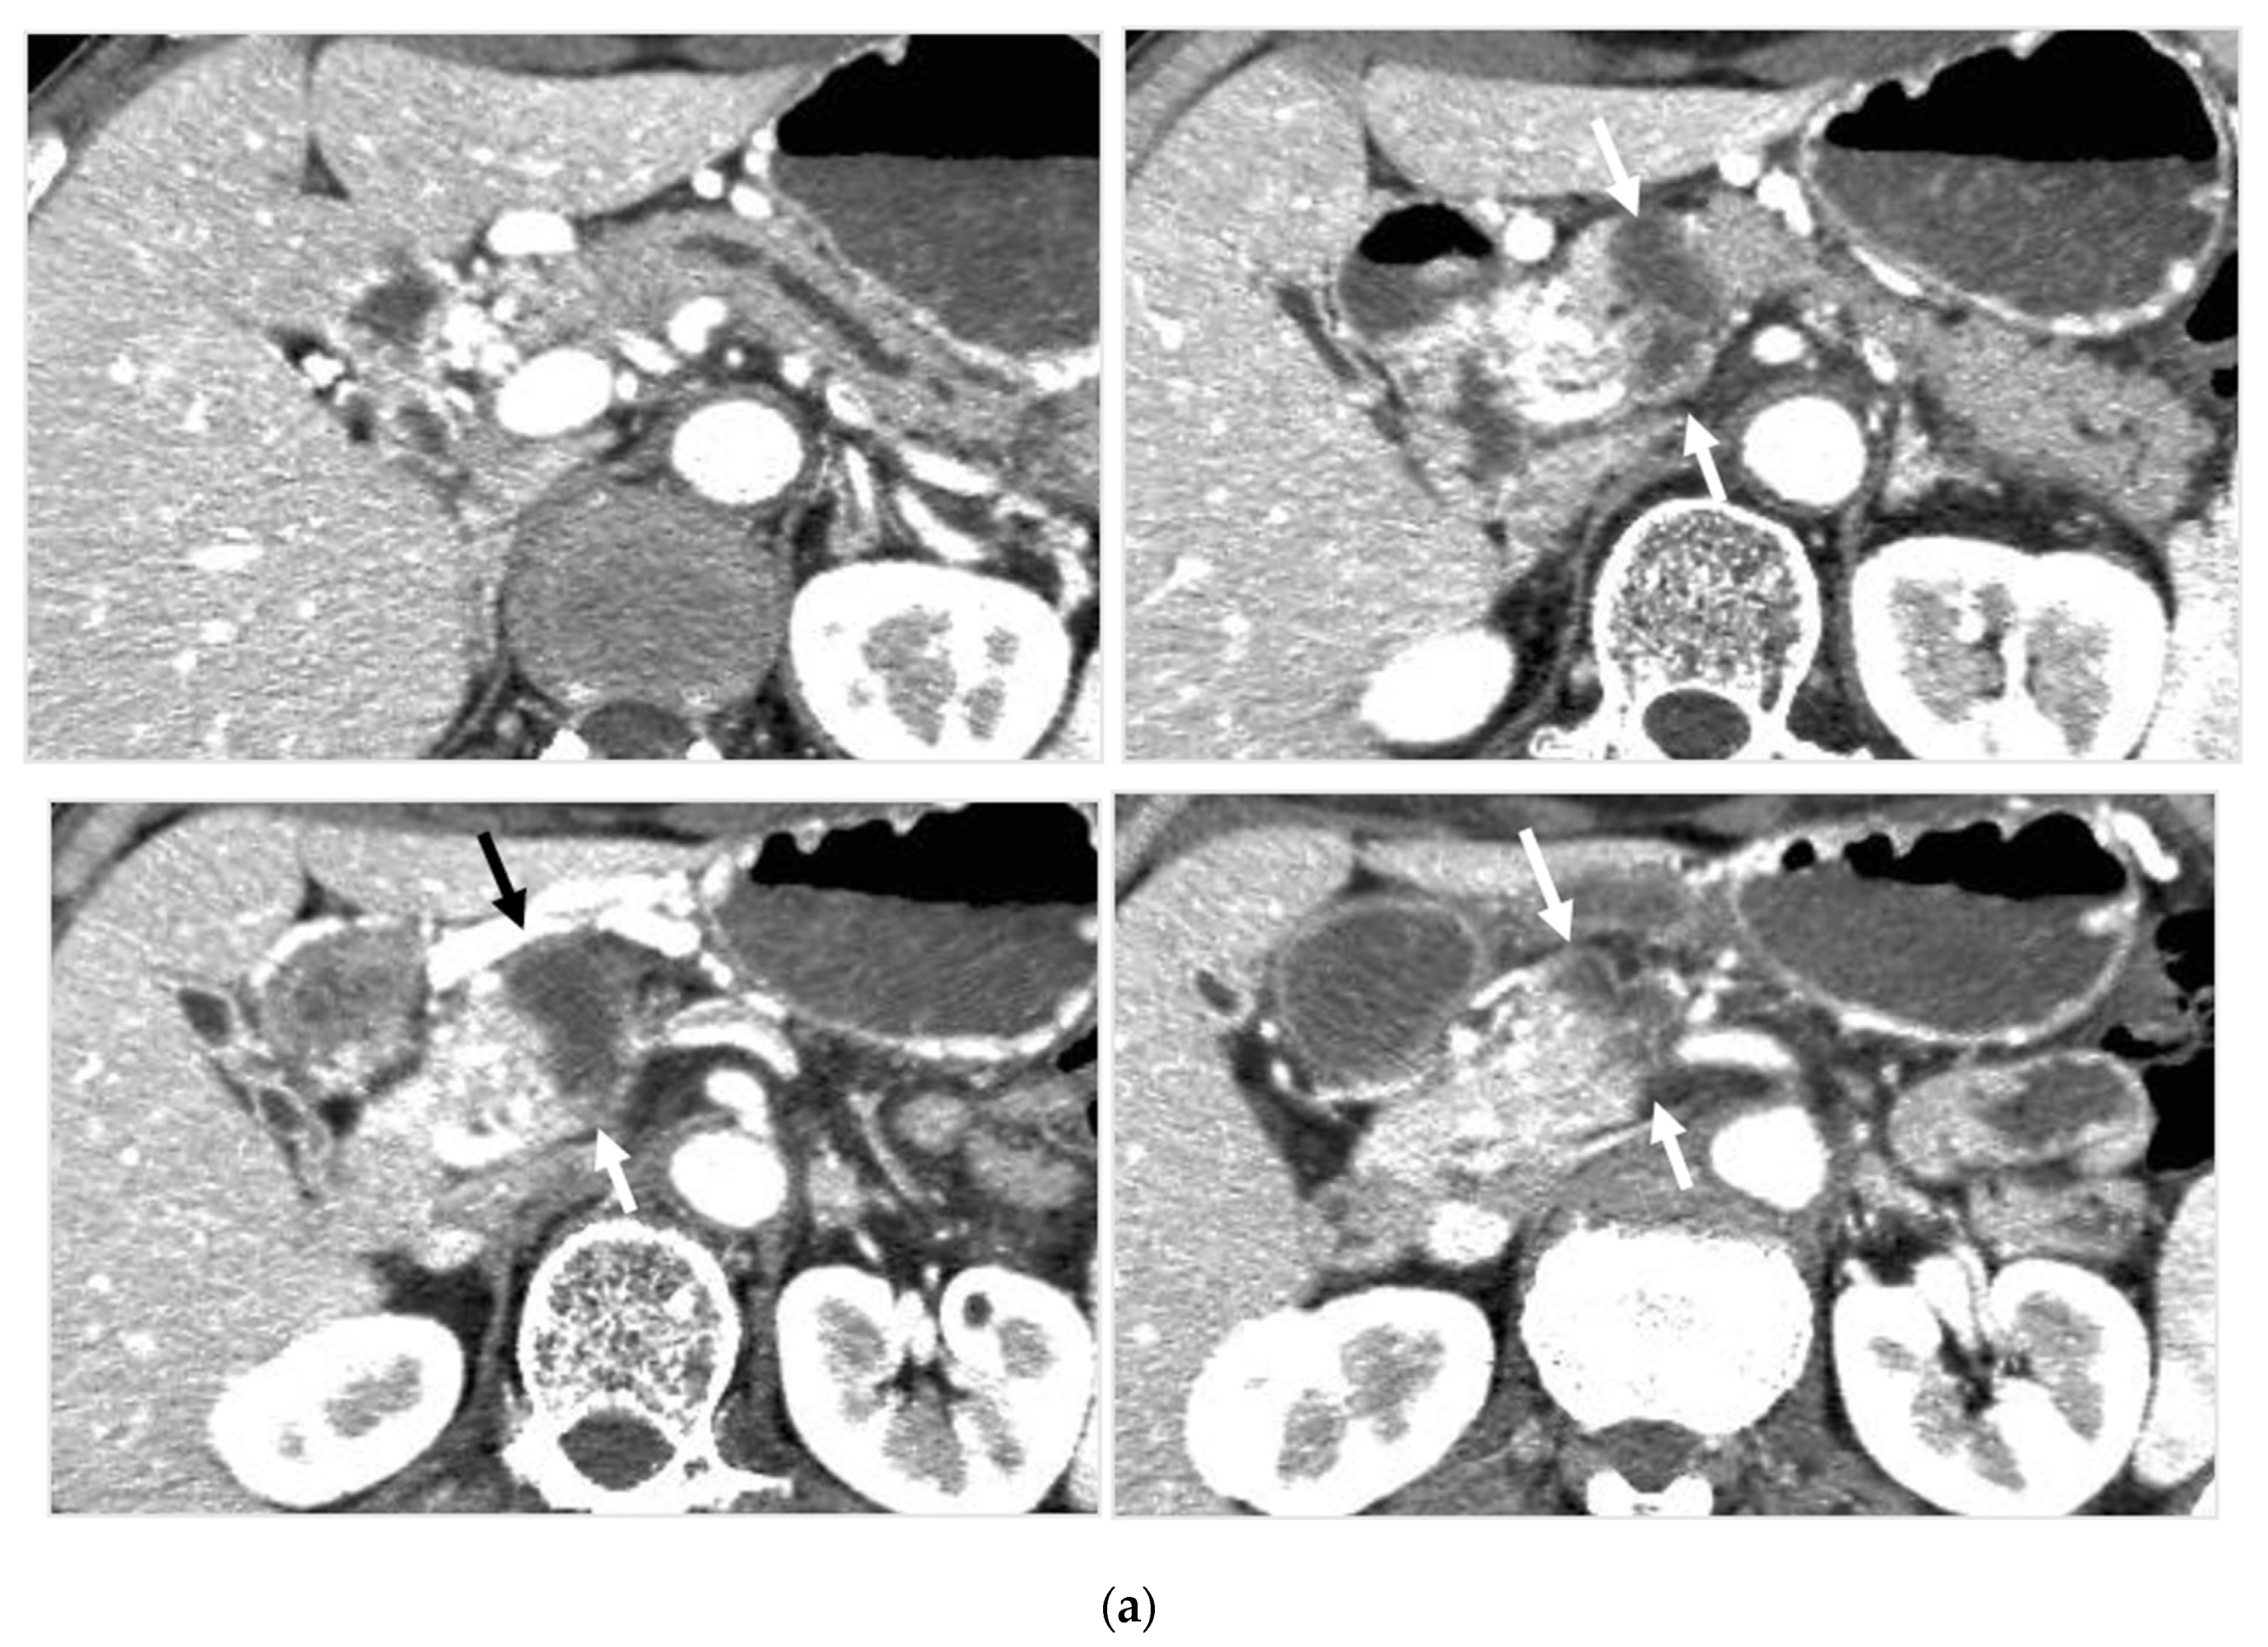

Identifying Supplying Arteries to Pancreatic Cancer

Method of Arterial Administration of Anticancer Agents

3.3. Patient Subgrouping According to Treatment Compliance

3.5. Tumor Response